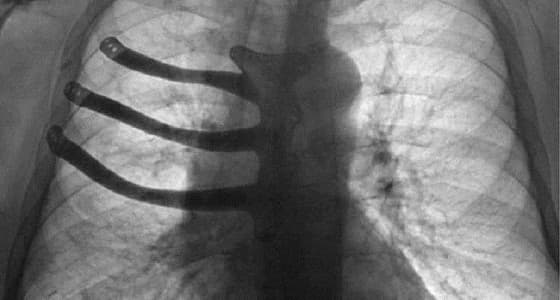

حيث قام الأطباء، باستئصال نصف عظم القص، وثلاثة أضلاع من القفص الصدري للمريض الذي يدعى " بيتر ماغزو " ، وذلك بعد إصابته بورم سرطاني.

حيث سمحت لهم الطابعة " ثلاثية الأبعاد " ، بطبع الأجزاء المستأصلة من سبيكة تيتانيوم، وتقليص فترة العملية إلى ساعتين، فيما تم استخدام التصوير المقطعي للقفص الصدري للمريض، أثناء عملية طبع هذه الأجزاء.